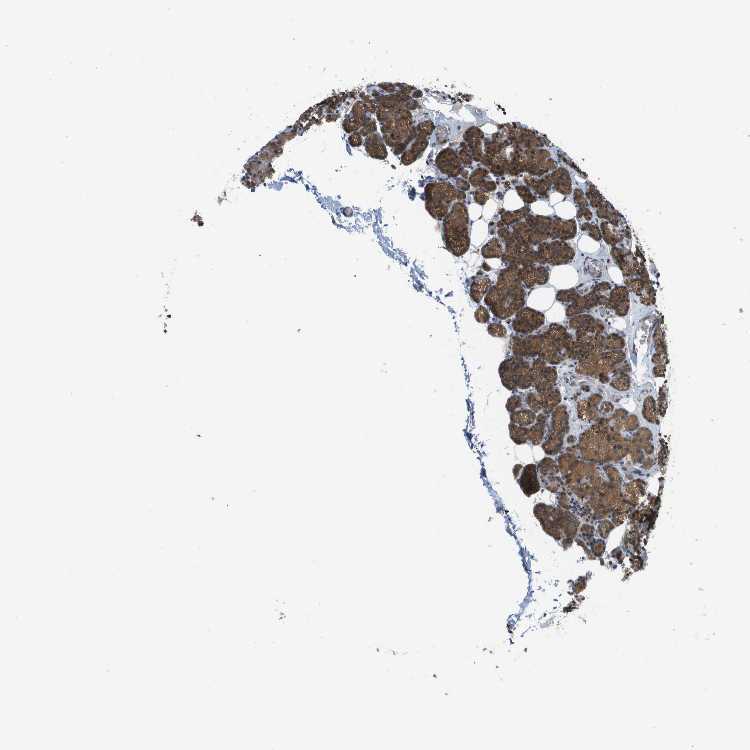

PARATHYROID GLAND - Antibody stainingi

Antibody staining in the annotated cell types in the current human tissue is reported as not detected, low, medium, or high, based on conventional immunohistochemistry profiling in selected tissues. This score is based on the combination of the staining intensity and fraction of stained cells.

Each image is clickable and will lead to virtual microscopy that enables deeper exploration of all samples and also displays staining intensity scores, fraction scores and subcellular localization as well as patient and tissue information for each sample.

Antibody HPA015696Antibody HPA017343

Glandular cells MediumHigh